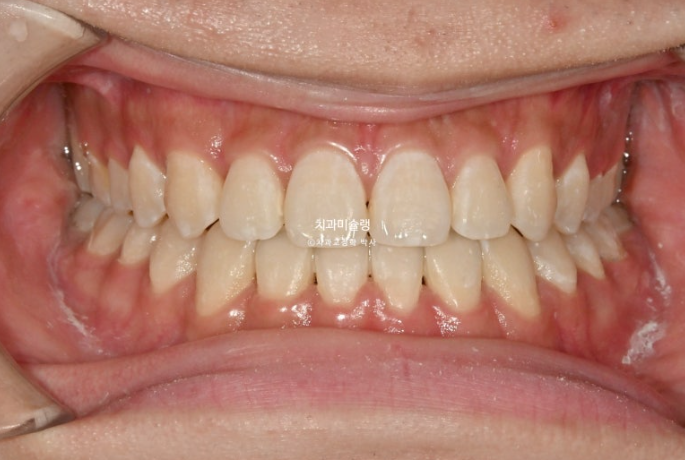

중심선은 정확히 맞으며 개방교합은 충분히 해소되었습니다.

반대교합은 개선되었고 교합관계는 1급을 달성

아래 앞니는 아래턱뼈 치조골 한계가 허용하는 극한까지 뒤로 들어갔습니다.

아래 어금니들은 가용한 사랑니 공간을 최대한 이용하며 뒤로 들어갔습니다.

2년 반동안 치근흡수도 없고 치근평행도는 좋습니다.